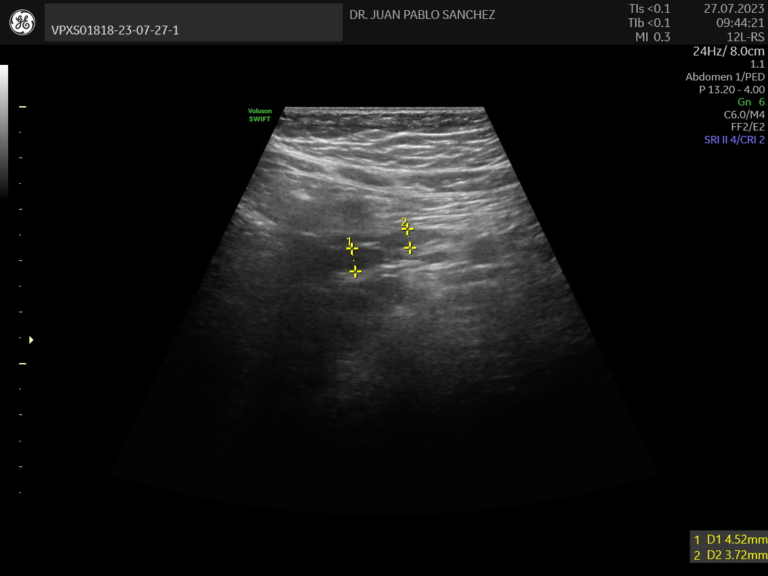

Ecografia de Canal Medular

Explora la columna y médula espinal en lactantes. Se usa para descartar anomalías como médula anclada o malformaciones congénitas como espina bifida.